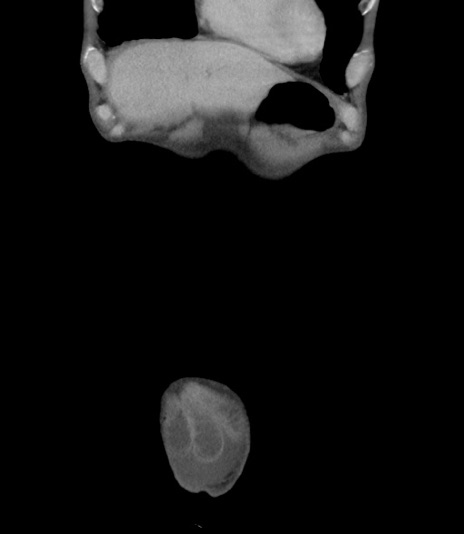

横断像